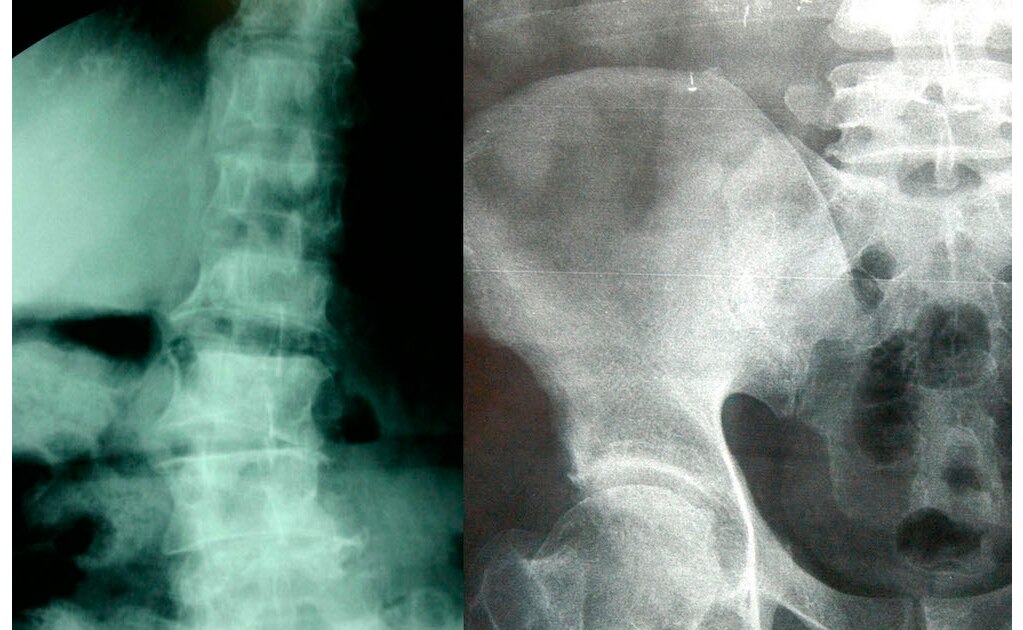

Describió que la osteoporosis se caracteriza por ser un padecimiento donde la calidad del hueso disminuye de forma microscópica, lo que ocasiona gradualmente cambios que deforman la osamenta o provocan fracturas. En el caso de la mujer, los huesos pierden estatura, cambia el lineamiento de la columna vertebral y, por consecuencia, provoca dolores intensos principalmente en piernas y cintura.